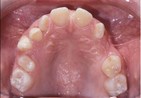

front view left buccal maxillary mandibular

Right Buccal View Frontal View Left Buccal View Maxillary View Mandibular View